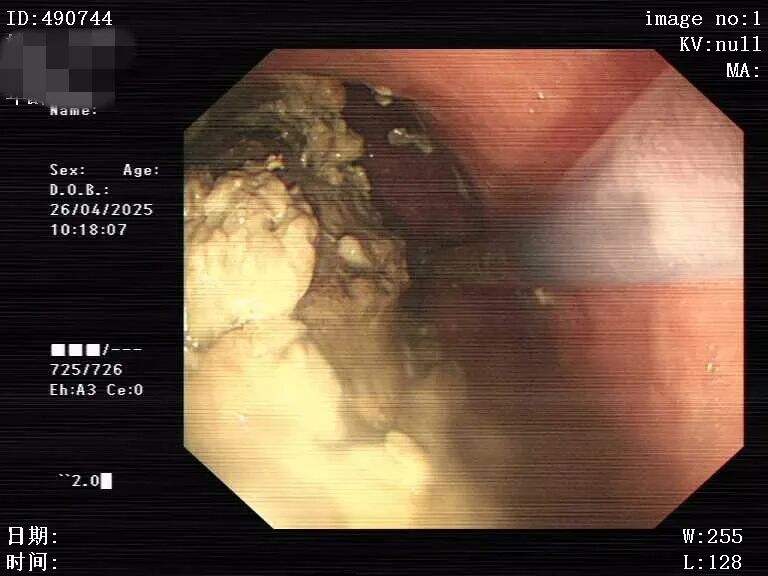

在诊疗过程中,患者不配合胃镜检查,出现反复拔镜的抗拒行为,这给诊疗工作带来了挑战。4月17日首次胃镜检查,发现齿状线上散在纵行糜烂灶,最长约15mm,相互不融合,胃底-体有大量食物残渣,考虑胃潴留,医院予禁食、胃肠减压、抑酸护胃、洗胃、补液等对症及支持治疗;26日再次进行胃镜检查,因患者不配合仅看到胃体有大量食糜潴留,食管有胃管留置,粘膜见部分食糜潴留,未见静脉曲张,继续予对症治疗;29日复查胃镜,见到胃体有潴留和一黑色球状固体,胃镜接触觉硬度高,无法绕过球状潴留物继续进入,因患者仍不配合检查而退镜,考虑胃石形成。在胃镜检查过程中发现有溃疡存在,且判断该溃疡与胃石长时间压迫密切相关。若胃石不能及时处理,溃疡面临反复出血或穿孔的极高风险,病情每拖延一刻,患者的生命健康就多一分威胁。

4月29日胃镜检查:胃潴留及胃石形成